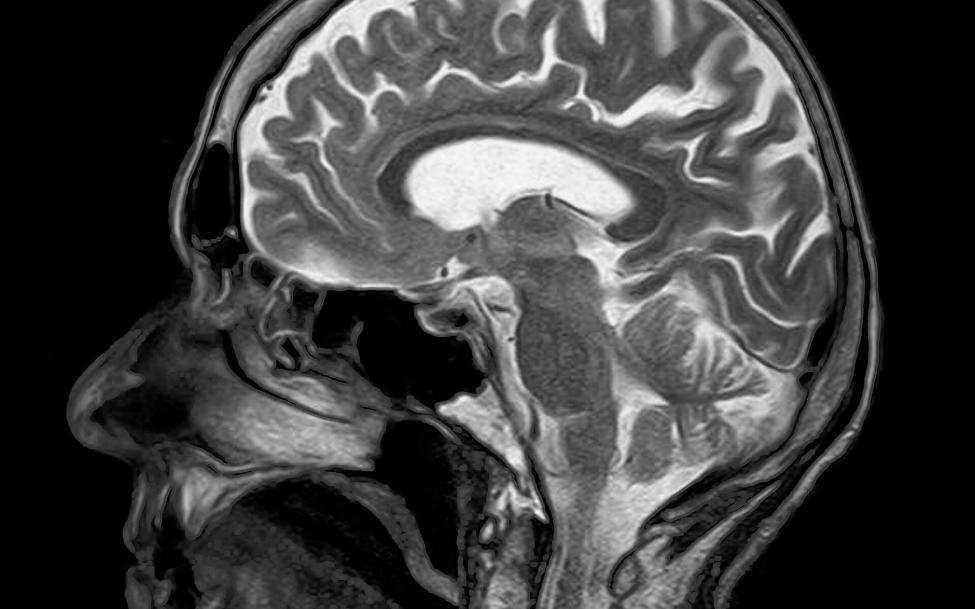

Après un accident de voiture Le coup du lapin ou coup de fouet cervical ou wiplash est un mécanisme d’accélération-décélération du transfert d’énergie vers le cou. Il peut résulter de collisions de véhicules à moteur par l’arrière ou sur les côtés, mais peut également survenir lors d’une plongée ou d’autres accidents. L’impact peut entraîner des…